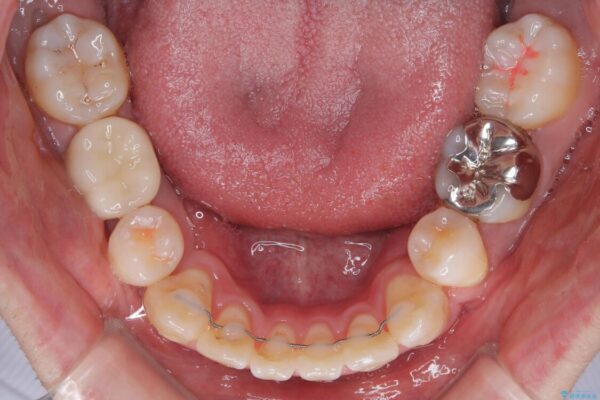

治療前

• 口元の突出感を改善!目立ちにくいワイヤー矯正で自信を持てる自然な横顔に 治療前画像

「横から見ると唇が前に出て見えるのが気になる…」 「マスクを外すのが恥ずかしい…」 そんな口元の突出感に悩まれてご来院された患者様。

精密検査の結果、上下左右の小臼歯4本を抜歯し、そのスペースに前歯を後方へ移動させる矯正治療をご提案しました。